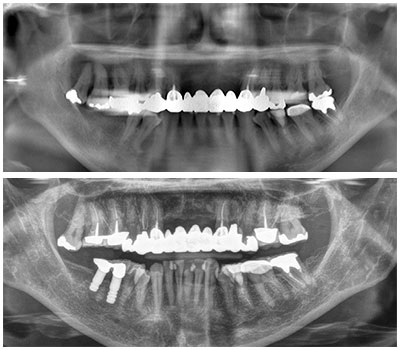

ctレントゲンで正確な診断 入れ歯 噛み合わせ 歯ぎしり 豊橋市 あしはら歯科医院

審美歯科治療 銀歯や虫歯などを 歯の神経の治療とともに全て白い歯で治療したケース 症例紹介 ごうぎんビル中島デンタルクリニック 広島市中区の歯医者

インプラント症例集 福島県郡山市 うすい歯科医院